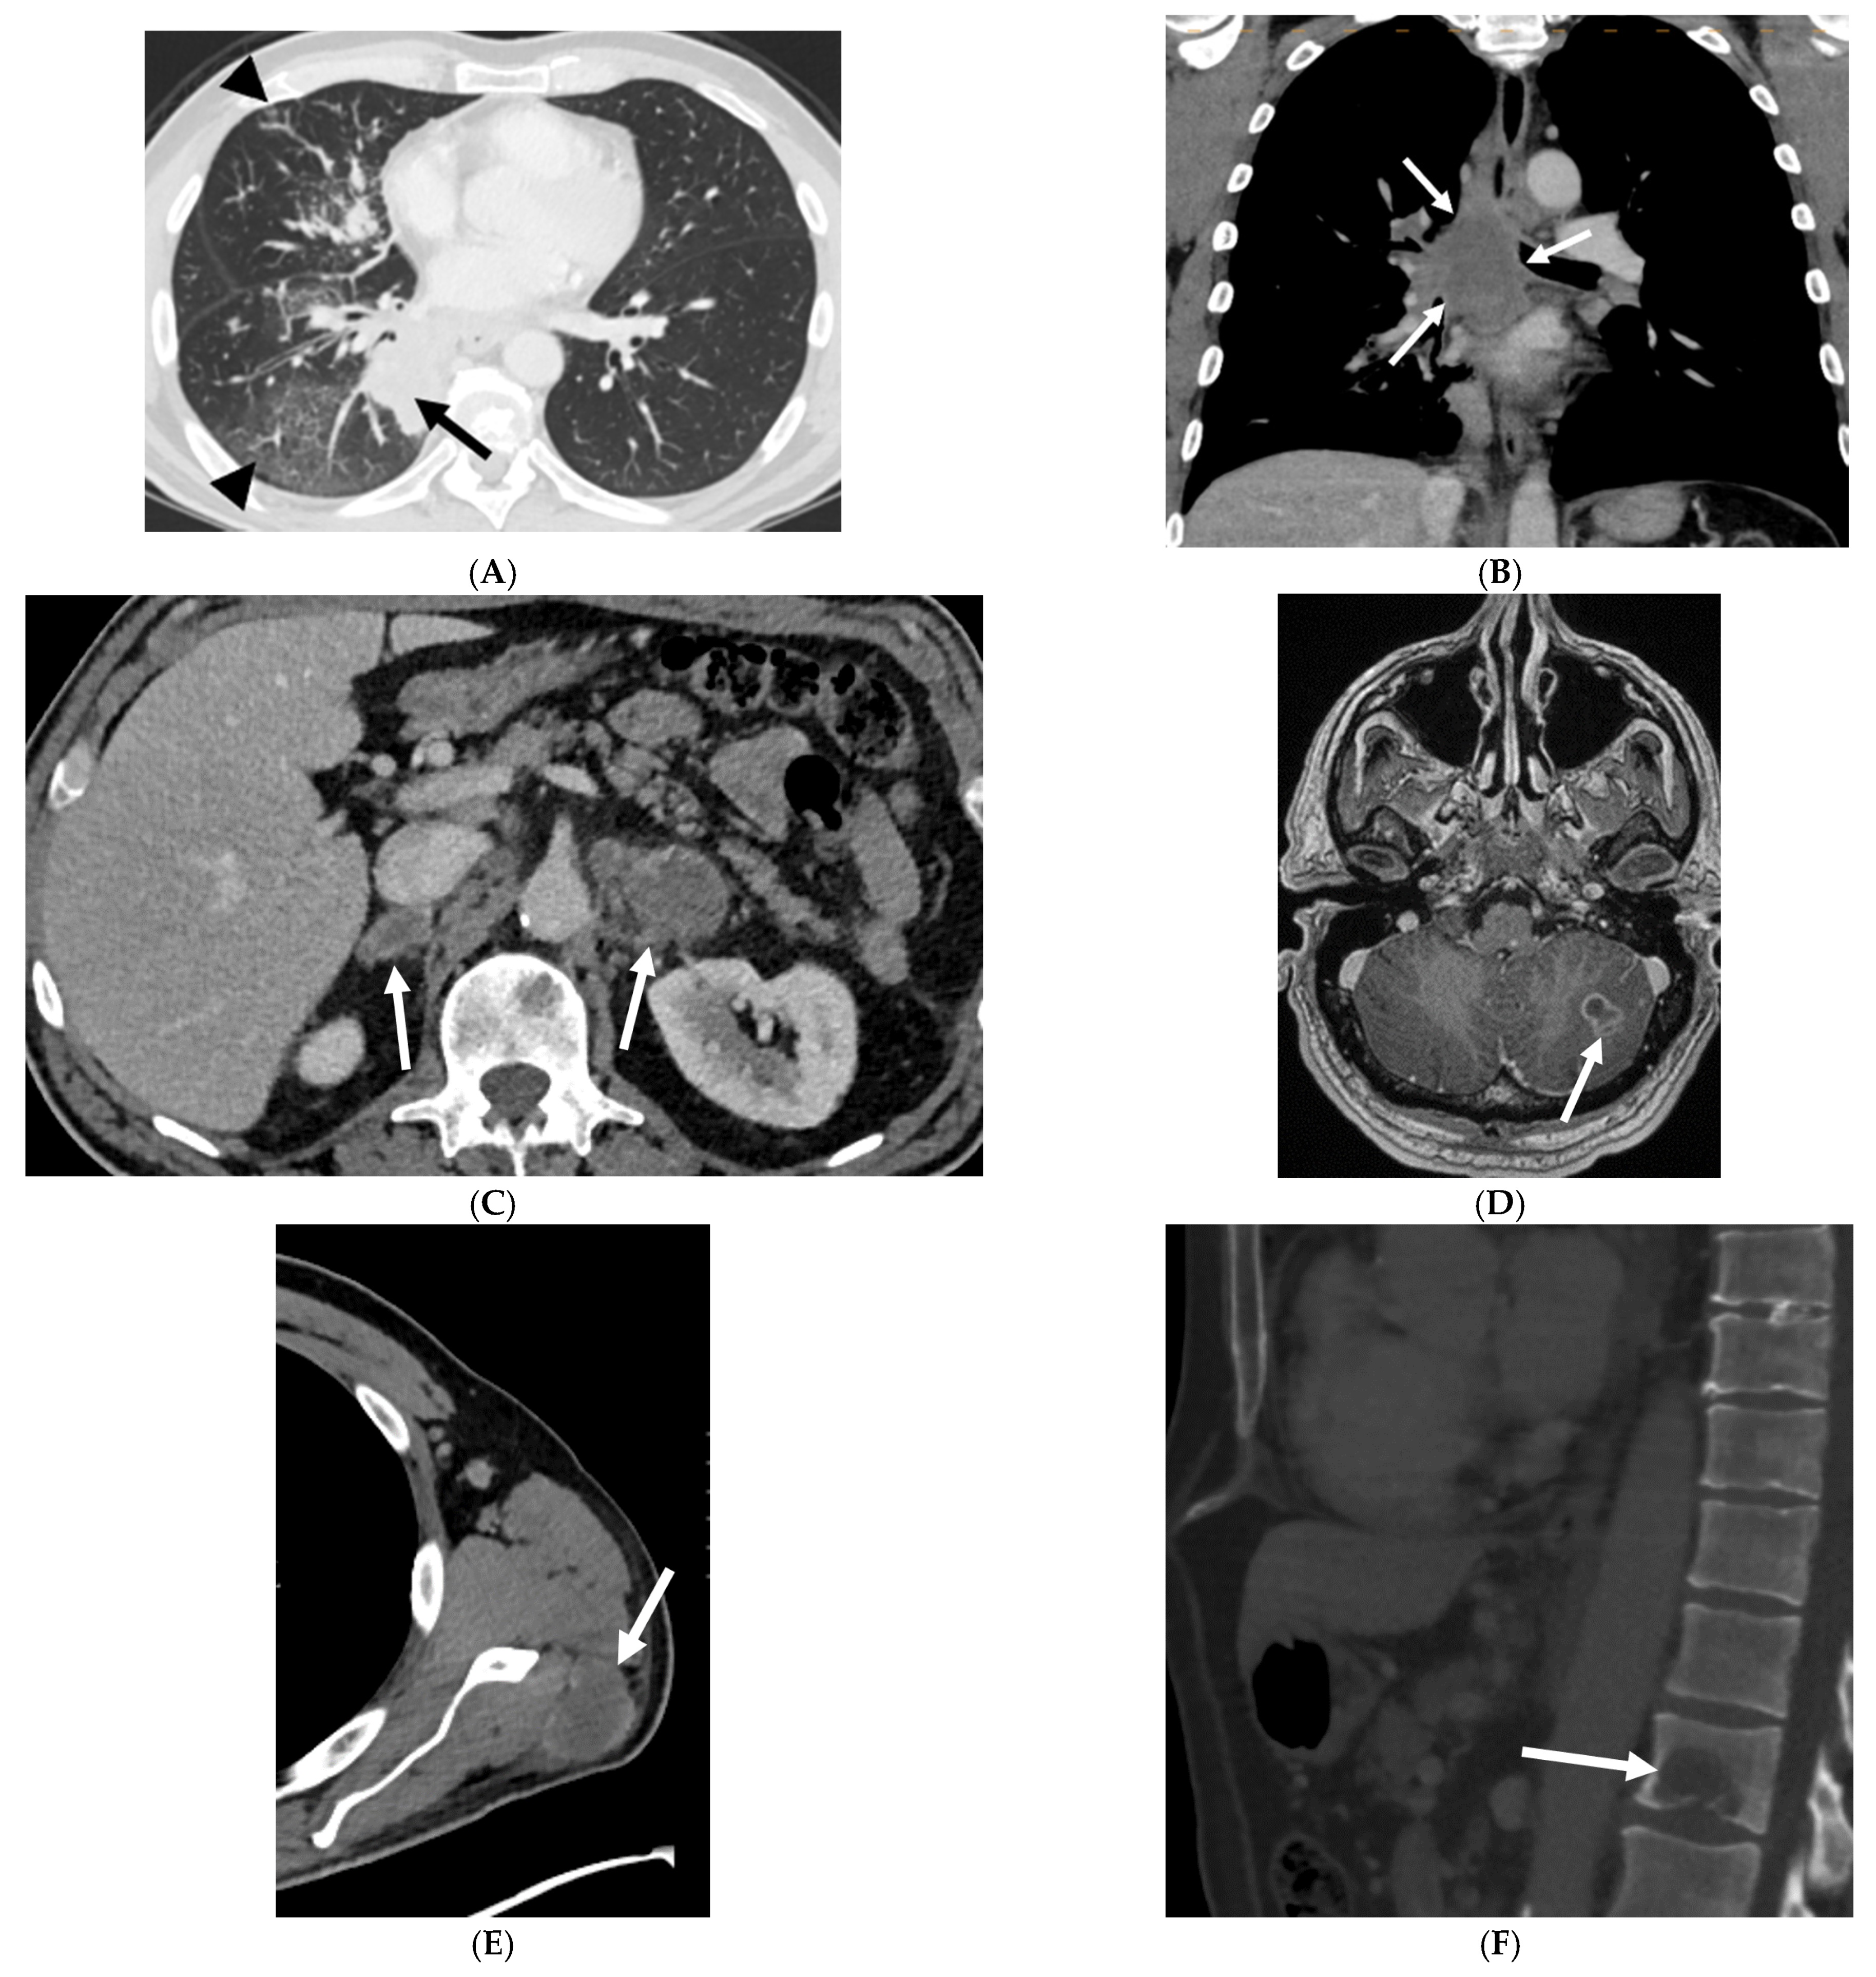

3.2.2. Imaging Features of the Primary Tumor

3.2.3. Patterns of Metastases